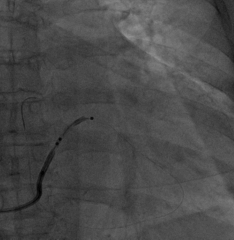

AP

LAO45

RAO30